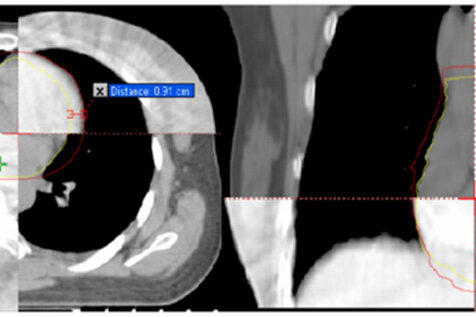

- The Use of Hybrid Imaging in Radiotherapy Treatment Planning